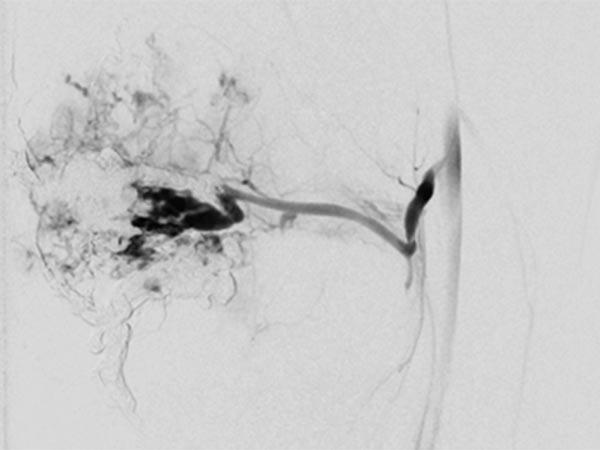

After renewed superselective catheterization of the AVM-feeding artery (lateral inferior genicular artery) ), the microcatheter is advanced to just before the nidus.

DSA image (roadmap technique) during re-embolization shows the freshly injected new additional embolic agent as black in the image.